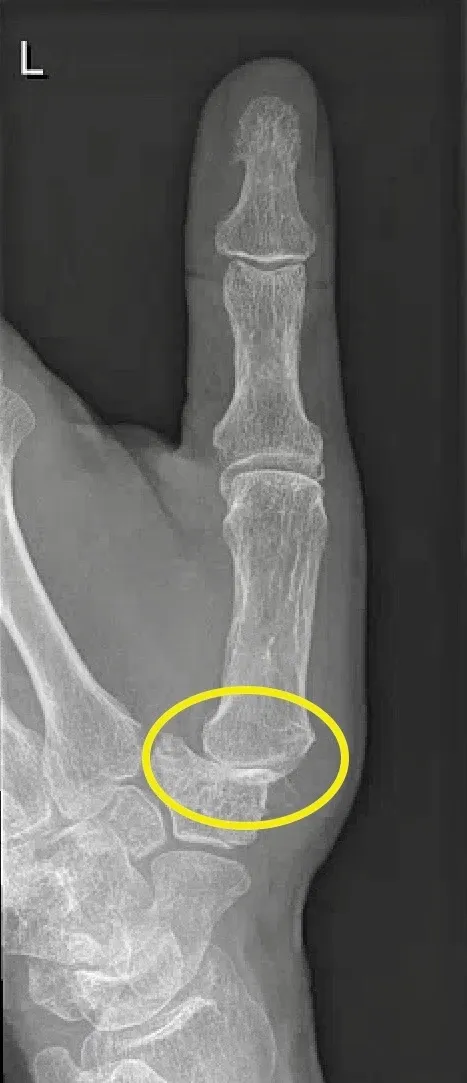

Skiduim

Wat is het?

Een skiduim is een scheur van het gewrichtsbandje (ulnair collateraal ligament) aan de binnenzijde van de duim, ter hoogte van het MCP-gewricht. Dit gebeurt meestal door een slag of val waarbij de duim naar buiten klapt. Het letsel kan:

- Gedeeltelijk of volledig gescheurd zijn

- Soms met een stukje bot me afscheuren (beenderige skiduim)

- Soms onder een pees terechtkomen, waardoor het niet spontaan kan genezen (Stener-letsel)

Behandeling

Volledige scheur of botbreuk:

- Operatie binnen 14 dagen

- Het ligament wordt opnieuw vastgezet met een anker

- Bij botfragment: kleine pinfixatie

- Bij laattijdige diagnose kan een peesgreffe nodig zijn

- Ingrepen gebeuren via dagziekenhuis, meestal onder plexusverdoving